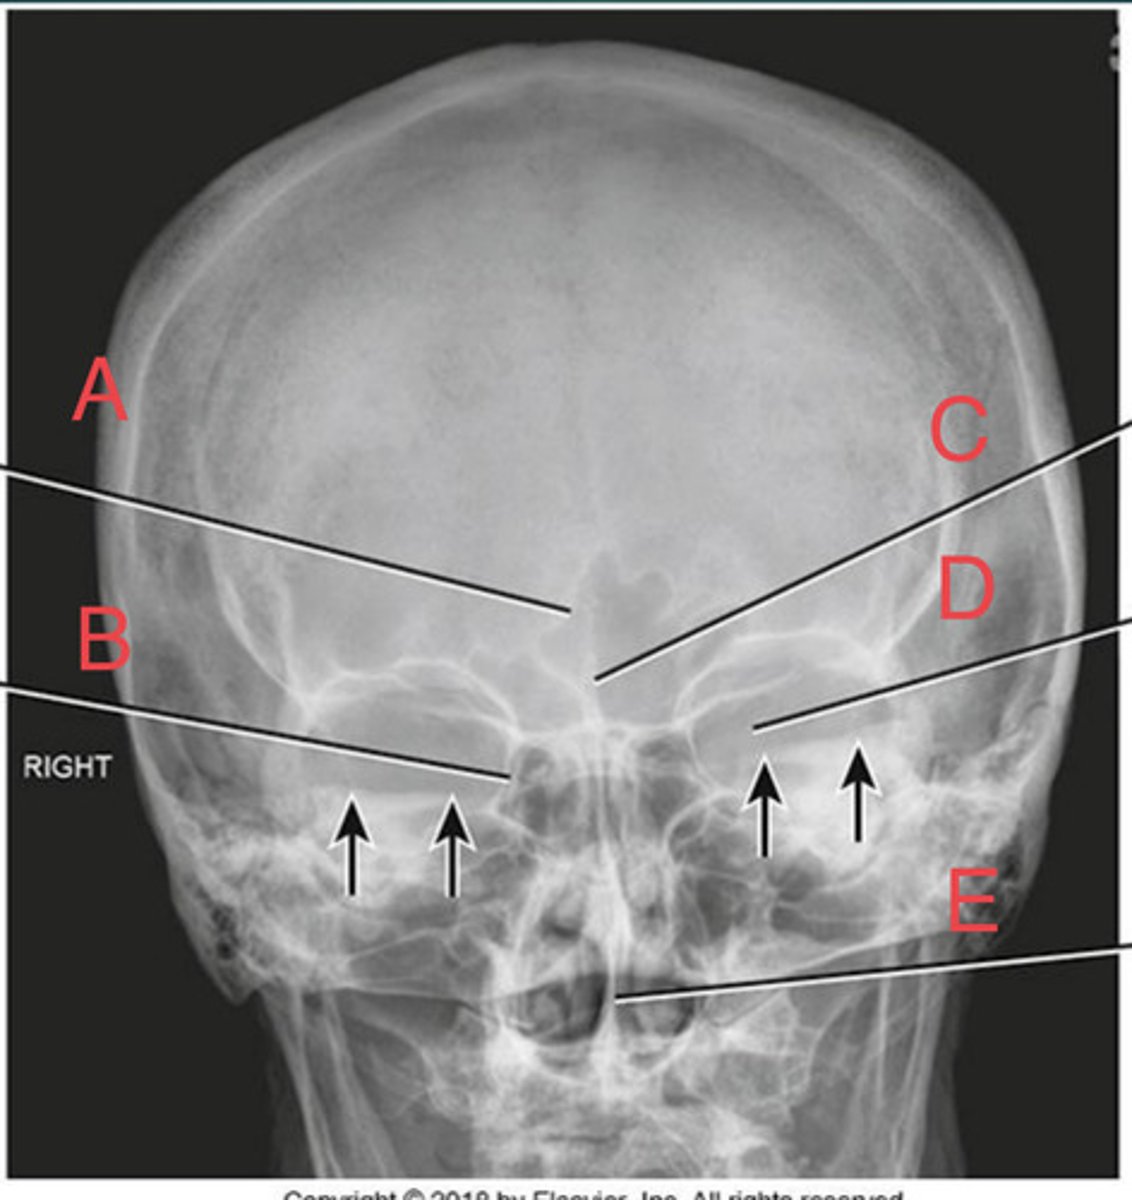

Lateral sinus

What position?

L. Orbital roofs

A.

L. Greater wings of sphenoid

B.

sella turcica of sphenoid

C.

L. Sphenoid sinus

D.

L. Rami of mandible

E.

L. Maxillary sinuses

F.

L. Ethmoid sinuses

G.

L. Frontal sinuses of frontal bone

H.